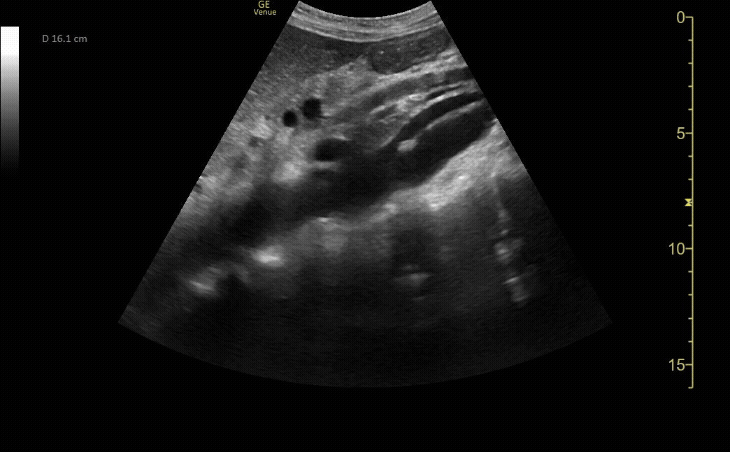

Abdominal Aortic Aneurysm that measured 8cm in size.

c/o Ginny Kim, MD